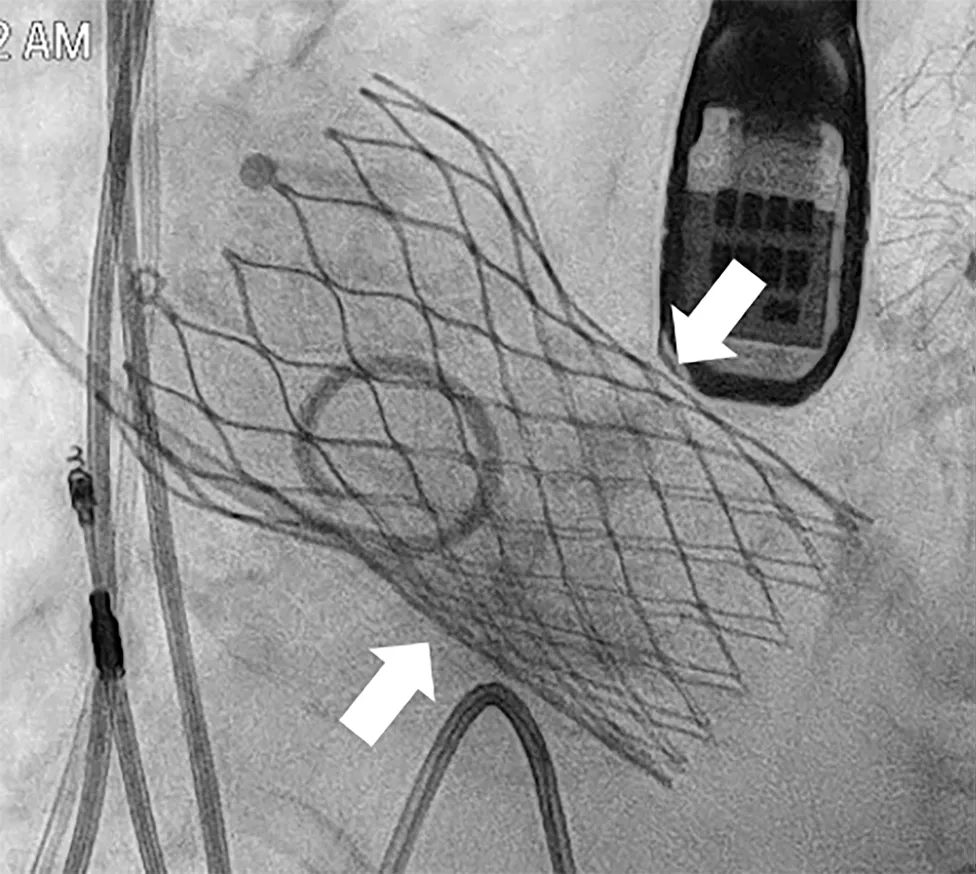

左前斜造影以获取最佳的瓣架对齐视角,可见 node 4 与 node 5 之间存在严重钙化,对应原Evolut R 瓣膜的瓣环上瓣叶区域。(图4,视频3)

图4 左前斜位瓣架对齐视图

在node4、node5之间可见严重钙化(白色箭头),对应原 Evolut R 瓣膜的瓣上小叶。

采用21 mm TRUE 球囊行主动脉瓣预扩。在钙化的 Evolut R 瓣叶水平可见明显的“球囊腰征”(图6,视频6),提示严重瓣叶钙化导致扩张受阻。

图6 逐步操作过程

(A)使用 21 mm TRUE balloon 行主动脉瓣预扩张。于钙化的 Evolut R valve 瓣叶水平可见明显“球囊腰征”(白色箭头),提示充盈过程中存在显著阻力。(B)植入 23 mm SAPIEN 3 Ultra RESILIA valve(S3UR)过程中发生球囊破裂。球囊远端可见造影剂积聚(白色箭头),形成类似“伞状”外观,提示存在水平撕裂。23 mm 瓣膜未完全释放(白色箭头)。(C)对侧入路行髂动脉造影。可见左侧髂总动脉夹层,但无活动性造影剂外渗(白色箭头)。(D)使用 23 mm TRUE balloon 对未完全扩张的 S3UR 瓣膜进行后扩张。(E)血管内干预后髂动脉造影。将 16F eSheath 回撤至左侧髂外动脉,并于夹层的髂总动脉内植入一枚 8 × 59 mm VBX 覆膜支架(白色双向箭头)。(F)血管内干预后股动脉造影。左侧股总动脉穿刺通路采用 7 × 50 mm Viabahn stent graft 进行封闭(白色双向箭头)。最终造影显示无造影剂外渗,血流通畅。

随后植入23 mm S3UR 瓣膜,其流出端与既往瓣膜支架的 node 4.5对齐。球囊扩张过程中发生破裂,导致瓣膜未完全扩张。球囊远端内造影剂积聚提示存在水平撕裂,形成“伞状”结构,使系统无法通过14F鞘管回撤(图6B,视频7)。

经左股动脉将输送系统及鞘管整体取出,随后更换为16F 鞘管以压迫可能的血管损伤。经对侧髂动脉造影显示左侧髂总动脉夹层,但无活动性造影剂外渗(图6C,视频8)。术中血流动力学始终稳定。

随后采用23 mm TRUE 球囊对未完全扩张的 S3UR 瓣膜行后扩张(图6D,视频9)。后TEE提示瓣膜位置良好,无瓣周漏(PVL)。

将16F鞘管回撤至左髂外动脉水平,并植入一枚8×59mm VBX 覆膜支架用以修复左侧髂总动脉夹层(图6E,视频10和11)。左股动脉穿刺口采用7×50mm Viabahn 覆膜支架进行封闭(图6F,视频12)。最终造影示无造影剂外渗,血流通畅(视频13)。